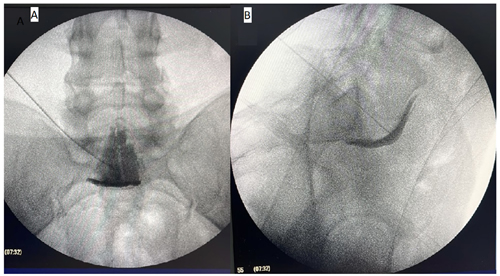

Figura 1

Figura 2

Materiales y métodos: En este estudio retrospectivo descriptivo, se analizaron 100 pacientes a los que se les realizó bloqueo del plexo hipogástrico superior guiado por fluoroscopia. Se obtuvo datos de dolor percibido y requerimiento de analgésicos a los 0, 1, 3 y 6 meses después el bloqueo, y se registraron las complicaciones como sangrado, infección, lesión neurológica, dolor persistente y toxicidad. La percepción del dolor se analizó mediante el modelo lineal generalizado con efectos mixtos para medidas repetidas.